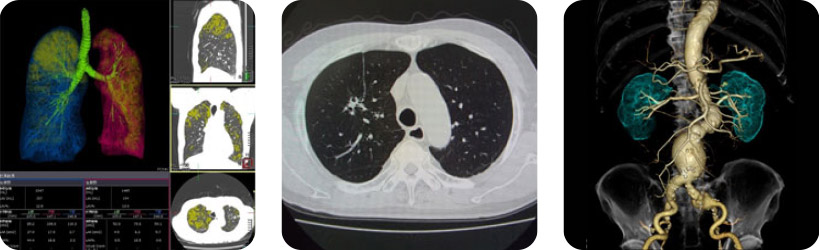

X線を使用して、身体の中の様子をコンピュータ処理して人体の精密な横断像(輪切り写真)を作り腫瘍や血管病変等を調べる検査です。当院では逐次近似法を用いて写真を作るため、従来の撮影に比べ少ない被ばく線量で検査が出来ます。

- 体の周りからエックス線をあて、体を通過したエックス線情報をコンピュータで解析し、連続した断層写真(輪切りの画像)を得る検査です。らせん状に連続撮影すること(ヘリカルスキャン)で全身を一度に検査することも可能です。輪切りの像だけでなく縦方向の像や横方向の像などあらゆる方向の画像を作ることができます。

- 病変を詳しく撮影するために、腕の静脈からヨード性造影剤という薬を注射しながら撮影することがあります。造影剤を用いることによって、病気の状態や血管や各臓器の血液の流れがわかりやすくなり、より正確な診断が可能になります。

- また、たくさんの薄い断層写真を得ることで、3D画像(立体的な画像)を作ることも可能です。